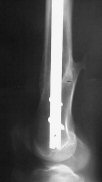

A. Difficult reductions, even in retrograde nailing (my preference, easier control of "small" distal fragment) and it is much, much harder to do it anterograde (Alex, do you have one good case in your collection of anterograde nailing in very distal fractures - as you have suggested that I

Malpositioning is much too common (recurvatum, varus - valgus).

B. Fixation loosening: distal cutting of the nail, non-unions do happen (cases attached).

Locking Plating has more distal screws than any nail, fixed angles and provides much better fixation, especially in osteoporotic bone.